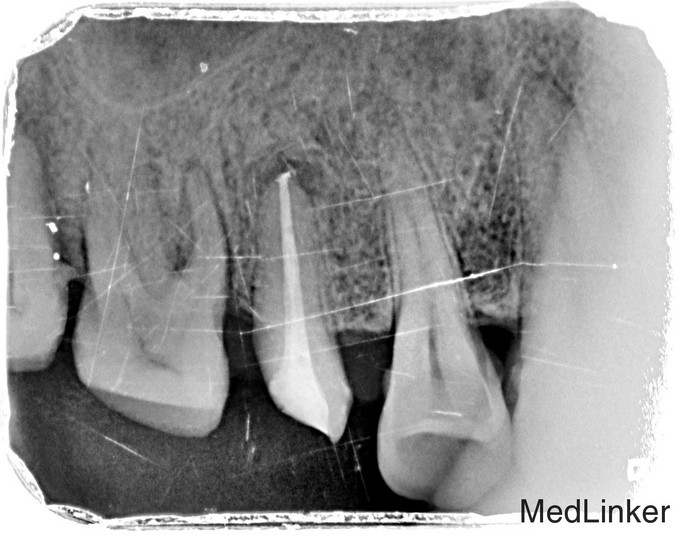

临床检查:15牙合面充填物部分脱落,探痛(+),冷(++),叩(+),松动度(-),牙周正常. 可探及穿髓点,有窦道。 辅助检查:X线示15龋坏累积髓腔,根尖周牙周膜增宽。根尖部阴影。

诊断:15根尖周炎 治疗:经患者知情同意后,15局麻去腐降牙合,开髓拔髓寻找根管口,建立直线通路,扩通根管,确定工作长度。S3/EDTA凝胶镍钛器械,低浓度次氯酸钠冲洗根管,预备至35/04,氢氧化钙诊间封药,一周后复诊,试主尖X线示恰充,试干根管,导AH-PLUS糊剂,VDW热压胶垂直加压根充,术后见根管恰充,暂封调合抛光观察。考虑桩冠修复。